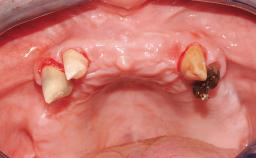

Conventional Loading of Eight Implants in the Maxilla and Final Restoration with a Full-Arch Gold-Ceramic FDP

A 35-year-old Caucasian female presenting with advanced periodontal disease involving both the maxillary and the mandibular dentition was referred for evaluation. The patient, a non-smoker in good general health, requested treatment for recurrent periodontal abscesses, tooth mobility, and discomfort during chewing, as well as restoration of her missing teeth with a fixed prosthesis to improve mastication and esthetics. All residual maxillary teeth exhibited plaque deposits, deep pockets, bleeding on probing, and class III mobility and were evaluated as hopeless. All residual mandibular teeth except tooth 37 could be maintained after periodontal therapy.

Case Type Edentulous Maxilla

Bone Augmentation Horizontal|Staged|Vertical

Augmentation Materials Autogenous block(s)